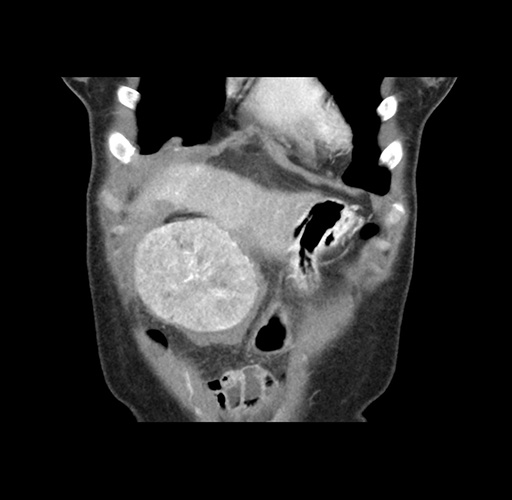

Imaging Analysis

Look through the patient's CT scan to identify any areas of concern for the necessary procedure.

Based on your CT findings, which issue(s) would give reason for "planned slowing down moment(s)" in this case?

Considering a standard left lateral sectionectomy procedure, what step(s) of the operation would you do differently in this case ?